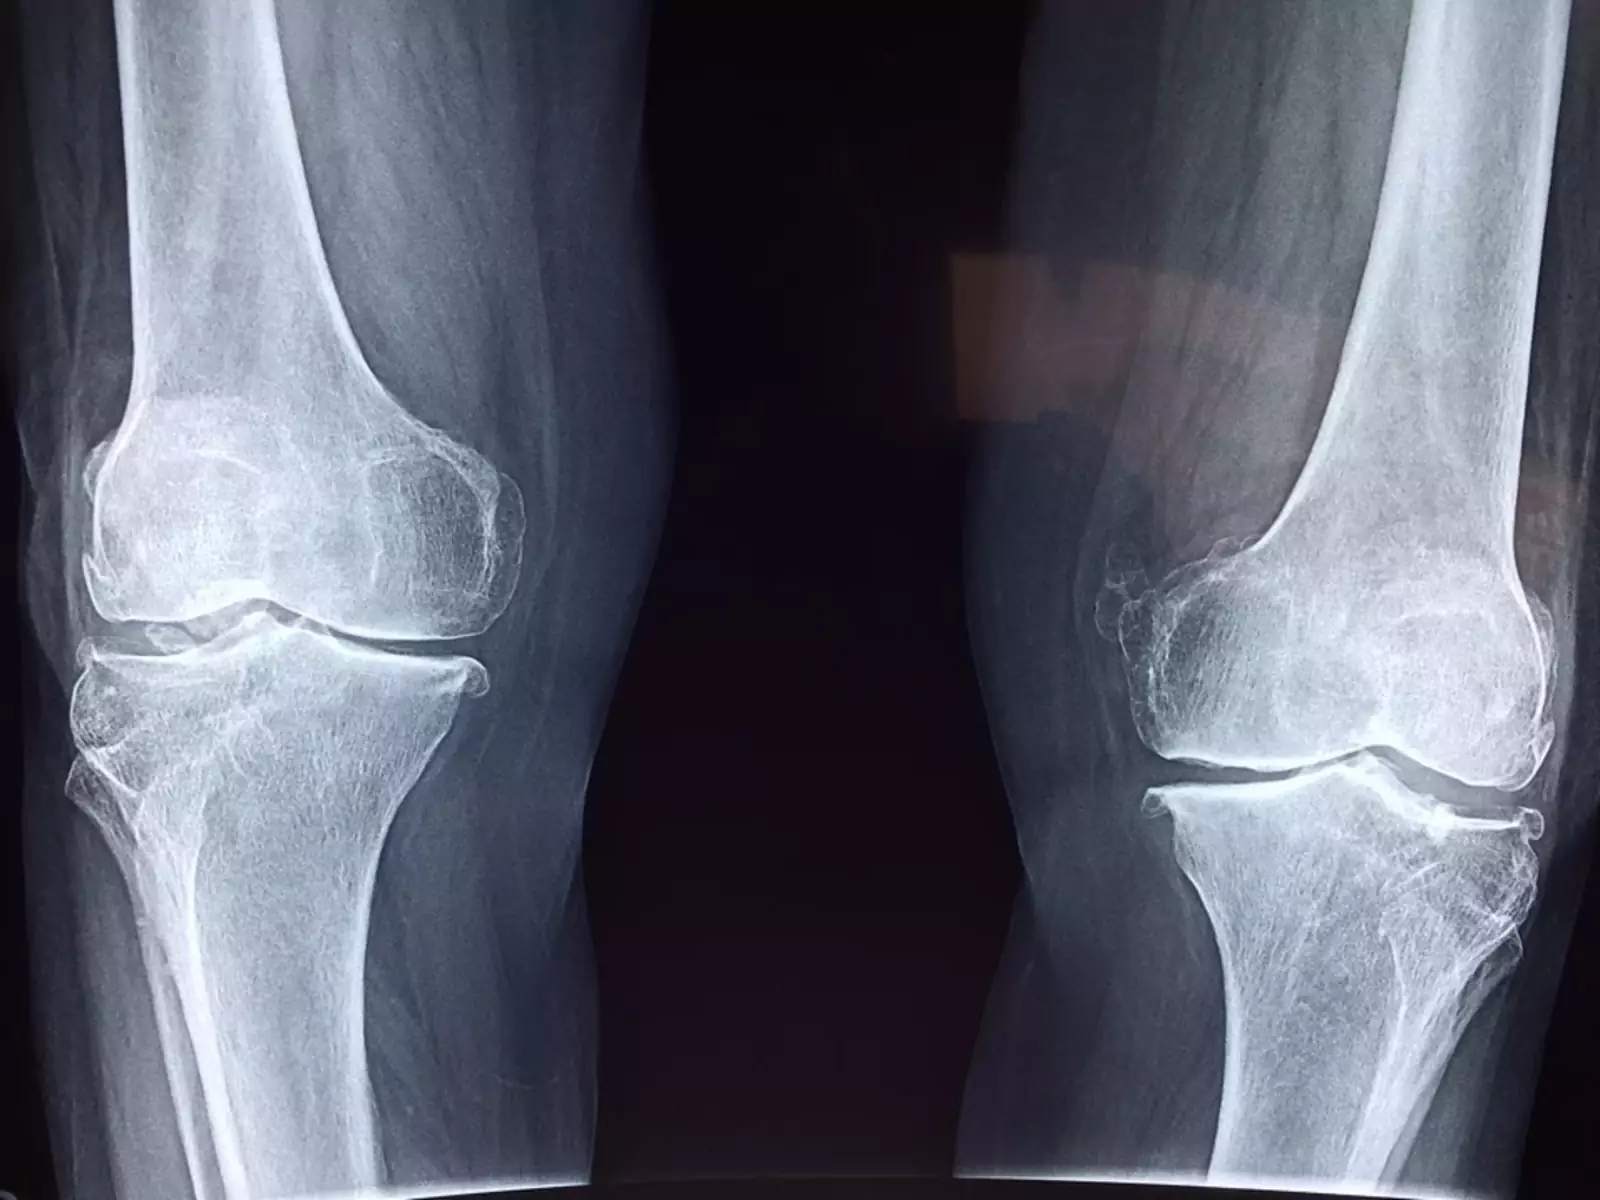

Перелом © pixabay.com